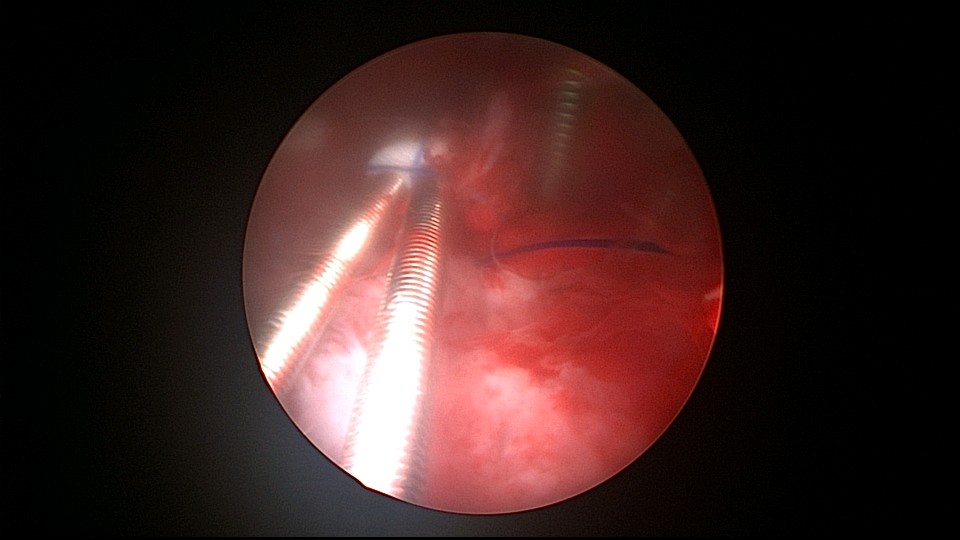

患者38岁,G4P2,剖宫产2次。2025年4月,停经40+天,计划外妊娠,要求终止妊娠并放置节育环,考虑终止妊娠后宫腔大,担心环移位或脱落,要求固定节育环。4-0不可吸收线将节育环缝合固定于宫腔上段后壁,缝合2针形成线圈固定节育环,没有打结推结。利用子宫肌层的卡压,缝合线圈不会自动松脱,形成有效固定,宫颈外口剪断线尾,留线较长,更利于固定。